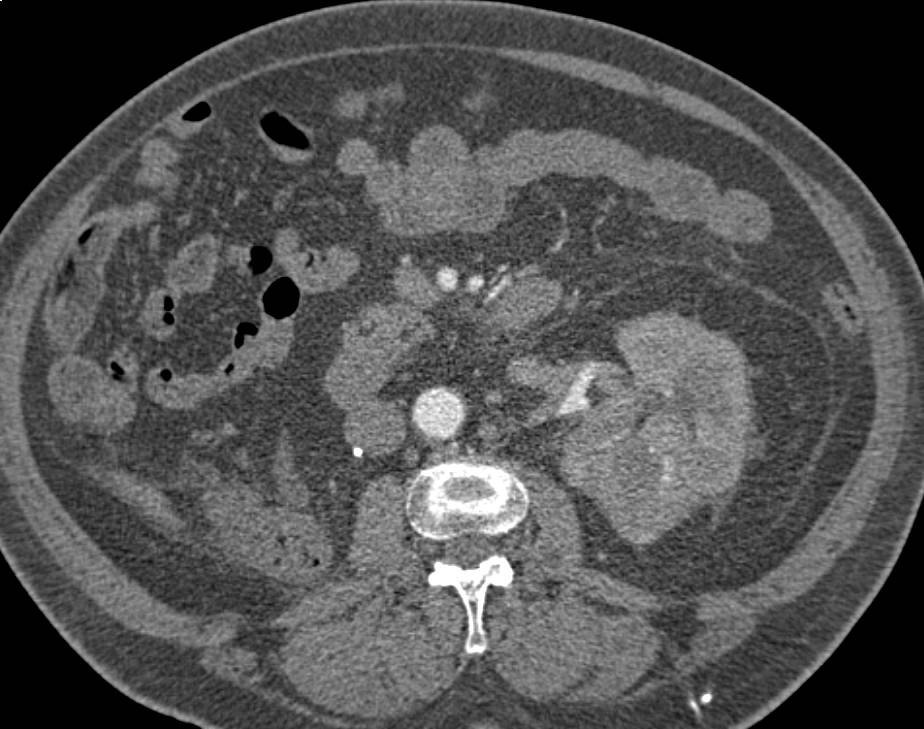

High Density Renal Cyst with Multiple Phases and Displays